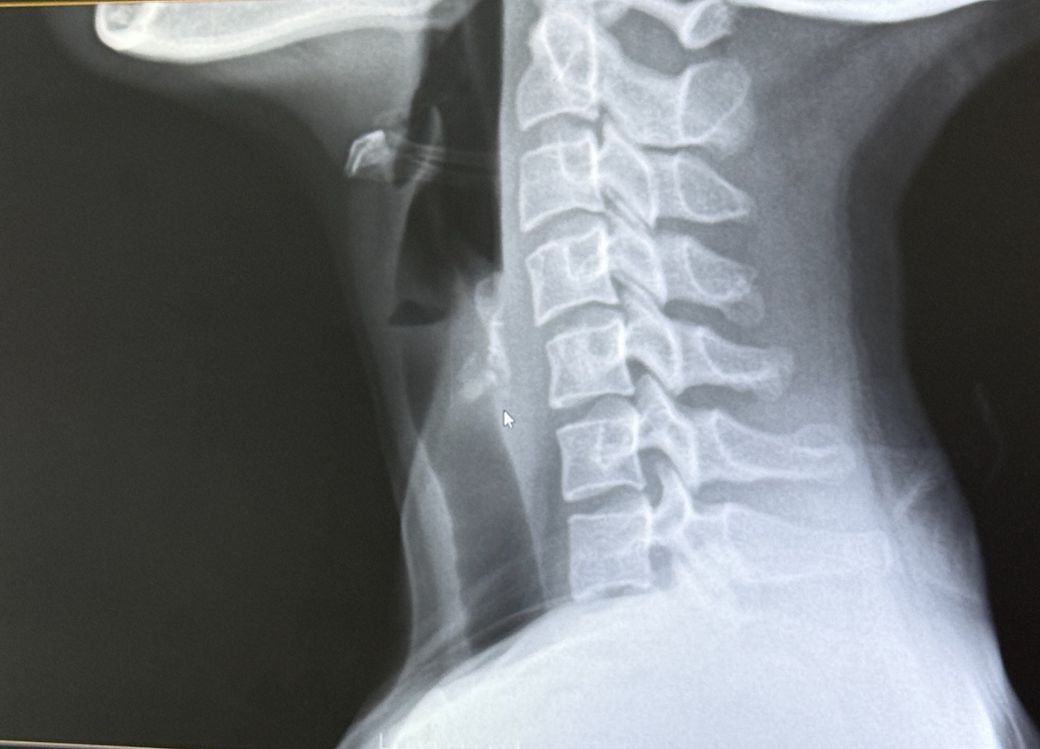

닭 가슴살 잔뼈를 삼킨 것 같은데 이비인후과에서는 안보인다고해서 내과에서 엑스레이를 찍었거든요. 확길히 뼈라고 단정지을 수는 없지만 지금 마우스커서가 있는 부분이 의심되긴한다라고 소견을 주셨는데 딱 저 부위가 불편한 부위라 걱정됩니다. 걱정으로 인한 이물감인지 잘 모르겠는데 혹시 선생님들께선 어떤 것 같나요

엑스레이상 검정색 세로로 긴 구조물이 기도이고 후면이 식도 위치하는데 비특이적인 음영이 관찰되므로 닭뼈와 같은 이물질 가능성이 있습니다. 식도 내에 닭뼈나 생선뼈가 걸리게 되면 식도 천공을 유발할 수 있어 위험할 수 있습니다. 따라서 정황상 닭뼈를 삼킨 것이 확실하고 통증이나 이물감이 있다면 금식을 유지하고 내시경 검사를 통해 확인해야 합니다. 답변이 도움이 되었기를 바랍니다.